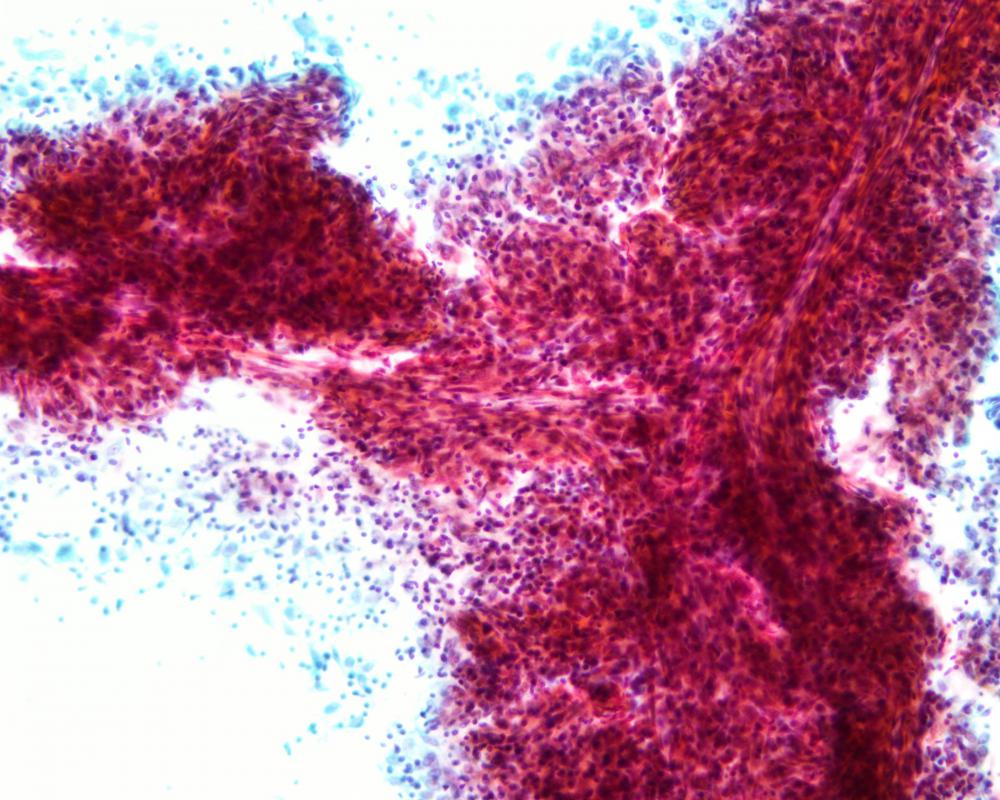

第36回日本臨床細胞学会九州連合会学会(大分)スライドカンファレンス症例3

種別:泌尿器

出題:鹿児島予防医学研究所 病理部 平木 翼

| 年齢 | 90歳代 | 性別 | 男性 |

| 採取部位 | 尿 | 採取方法 | 自然尿 |

| 検体処理法 | LBC 法 (サイトリッチレッド、BD) |

臨床所見

既往歴:高血圧症、高脂血症、高尿酸血症

現病歴:半年前から続く肉眼的血尿を主訴に、当院泌尿器科を受診された。超音波検査では膀胱頂部後壁、右側壁、左側壁、内尿道口内部に最大径 4 cmの多発性腫瘍を認めた。

| 正解 | 2.腺上皮への分化を伴う高異型度尿路上皮癌 |

▼選択肢及び投票結果

| 1.膀胱原発腺癌 | 30件 | (46.9%) | |

| 2.腺上皮への分化を伴う高異型度尿路上皮癌 | 21件 | (32.8%) | |

| 3.神経内分泌癌 | 0件 | (0.0%) | |

| 4.胃癌の転移 | 2件 | (3.1%) | |

| 5.前立腺癌の直接浸潤 | 11件 | (17.2%) | |

| 投票総数 | 64件 | (100%) |